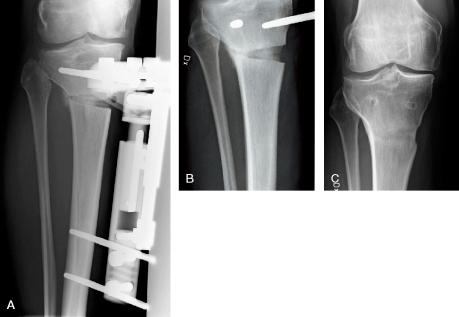

Bisphosphonates increase the callus size and strength in animal fracture studies. In a human non-randomized pilot study of high tibial osteotomies in knee osteoarthritis, using the hemicallotasis (HCO) technique, bisphosphonates shortened the healing time by 12 days. In the present randomized study, we wanted to determine whether a single infusion of zoledronic acid reduces the time to clinical osteotomy healing. Results from the same trial, showing improved pin fixation with zoledronate, have been published separately.

46 consecutive patients (aged 35-65 years) were operated. At 4 weeks postoperatively, the patients were randomized to an intravenous infusion of either zoledronic acid or sodium chloride. Dual-energy X-ray absorptiometry (DEXA) was performed 10 weeks postoperatively. Radiographs were taken at 10 weeks and every second week until there was radiographic and clinical healing. Healing was evaluated blind, with extraction of the external fixator as the endpoint. At 1.5 years, an additional radiograph was taken and the hip-knee-ankle (HKA) angle measured to evaluate whether correction had been retained.

All osteotomies healed with no difference in healing time between the groups (77 (SD 7) days). Bone mineral density and bone mineral content, as assessed with DEXA, were similar between the groups. Radiographically, both groups had retained the acquired correction at the 1.5-year follow-up.

In this randomized comparison, a single infusion of zoledronic acid increased the pin fixation of the external frame but did not shorten the healing time. In both groups, the external fixator was extracted almost 2 weeks earlier than in previous studies. The early extraction did not cause a loss of correction in either group.